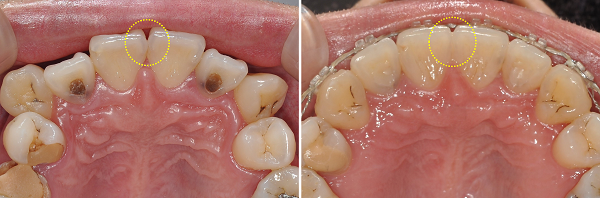

① 상악 전치부 순면 다듬기 — 브라켓 부착 준비

상악 전치부의 순면에 변연융선이 과하게 발달해 있어 심미적 문제는 물론, 브라켓을 정확한 토크·높이로 부착하기가 어려웠습니다.

따라서 **에나멜 성형(enameloplasty)**을 진행해 평탄한 부착면을 확보했습니다.

④ 상악 중절치 사이 치간삭제(IPR)

상악 중절치 인접면 형태가 비대칭·불규칙하여,

• 배열 안정성

• 접촉면 형성

• black triangle 예방

을 위해 **미세 치간삭제(IPR)**를 정밀하게 수행했습니다.